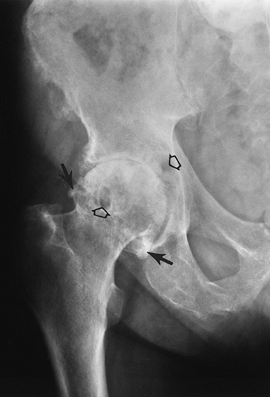

![]() |

FIGURE 4-37 Osteoid osteoma. (A) Routine radiographs demonstrating medial joint space widening (arrow) caused by soft tissue reaction. (B) Axial T2-weighted MR image showing focal increased signal along the femoral neck (arrow). (C) CT clearly demonstrating osteoid osteoma (arrow). Note the anterior soft tissue thickening (open arrow).